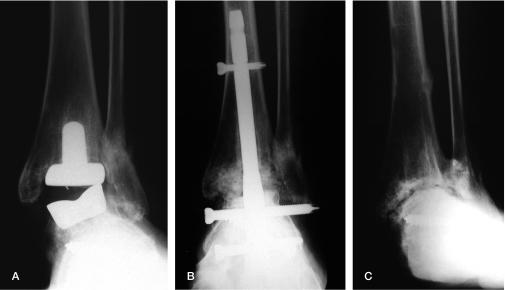

Between 1994 and 2005, salvage arthrodesis was performed on 18 ankles (18 patients). Diagnosis was inflammatory joint disease (IJD) in 15 cases and osteoarthritis (OA) in 3. Tibio-talar fusion was performed in 7 ankles, and tibio-talocalcaneal fusion in 11. Serial radiographs were studied for time to union. Clinical outcome at latest follow-up was measured by the AOFAS score, the foot function index (FFI) and by VAS scores for pain, function, and satisfaction.

Blade plates were used in 7 ankles (4 IJD, 3 OA); all united. Nonunion developed in 7 of the 11 rheumatic ankles stabilized by other methods. 11 patients (8 fused ankles, 3 nonunions) were available for clinical evaluation. Their mean AOFAS score was 62 and mean overall FFI was 70. VAS score for pain was 20, for function 64, and for satisfaction 74. The scores were similar in united and non-united ankles.

Blade plate fixation is successful in salvage arthrodesis for failed TAA. A high nonunion rate was found after salvage ankle arthrodesis in IJD with other methods of fixation. Clinical results were fair to good.